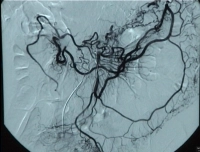

Video clip: SMA occlusion close to its origin with occlusion of the celiac trunk